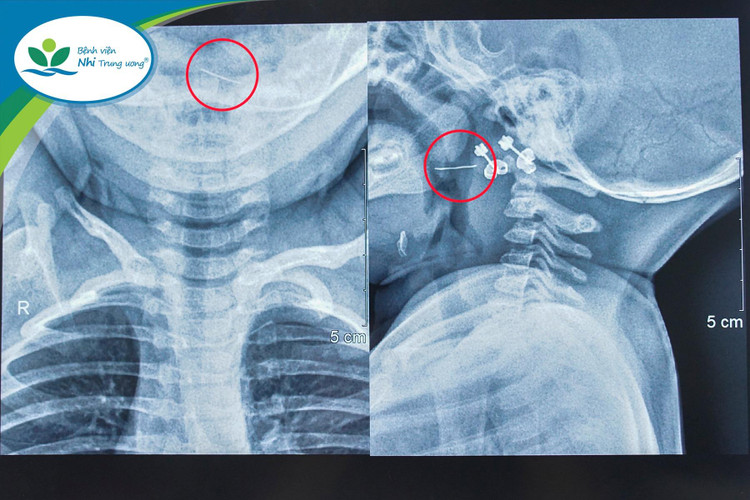

Tại đây, trẻ được các bác sĩ chỉ định chụp X-Quang cổ ngực thì được chẩn đoán theo dõi dị vật kim loại vùng sàn họng – miệng và chuyển đến Bệnh viện Nhi Trung ương để tiếp tục điều trị.

Tại Bệnh viện Nhi Trung ương, sau khi trẻ được thăm khám, soi họng và đọc kết quả phim X-Quang, các bác sĩ xác định có dị vật kim loại đâm xuyên qua Amidan bên trái của trẻ.